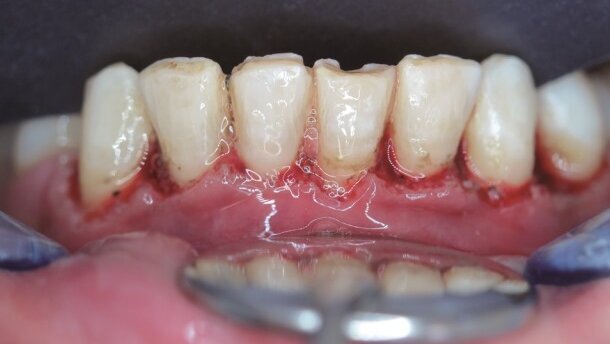

Budowa dziąseł łuku górnego była nierówna, a w okolicy zębów 21-22 i 22-23 widoczny był przerost dziąseł spowodowany niewystarczającą higieną oraz prawdopodobnie obecnością korony na metalu na zębie 22. Ponadto, badania przypadków wykazały, że w celu osiągnięcia optymalnego wskaźnika stosunku długości do szerokości 62-80%, przed przystąpieniem do zamknięcia diastem należy wykonać wydłużenie korony. Standardowo odległość od brzegu dziąsła do połączenia cementowo-szkliwnego wynosi 1 mm. Opisane wyżej problemy można rozwiązać usunięciem nadmiaru dziąsła poprzez dokładnie zaplanowane cięcia. Jeśli wydłużenie korony planowane jest w celu przedłużenia zęba, należy rozważyć zwiększenie szerokości biologicznej oraz nieprzekroczenie jej, gdyż może to doprowadzić do zniszczenia tkanek przyzębia.

W związku z tym, przed przystąpieniem do zabiegu dokonano pomiarów głębokości szczelin dziąsłowych oraz – zgodnie z planowanymi wymiarami zęba – zanotowano szerokość, wysokość oraz ich stosunek (Tab. 1). Idealne proporcje wynoszą 0,8-0,9. Po ustaleniu proporcji, wodoodpornym markerem zaznaczono na powierzchni dziąseł granice cięcia (Ryc. 7). Ponieważ długość korony klinicznej była mniejsza od korony anatomicznej oszacowano, że należy usunąć ok. 2 mm dziąsła (Ryc. 8).

Tkanki dziąseł pacjentki charakteryzowały się grubym biotypem oraz odpowiednio grubym dziąsłem związanym. Rekonstrukcję dziąsła wykonano, używając następujących parametrów: średnia moc na wyjściu wynosiła 2,5 W, czas trwania impulsu to 700 µsec (tryb S), częstotliwość powtarzania impulsu wynosiła 50 Hz z zastosowaniem końcówki MZ5 przy minimalnym użyciu wody (powietrze: 10 – woda: 10). W pierwszej kolejności usunięto nadmiary dziąseł wg zaznaczonego wcześniej wzoru (Ryc. 9). Na koniec stworzono estetyczną symetrię dziąseł, a następnie przeznaczono 2 tygodnie na wygojenie do następnej fazy leczenia (Ryc. 10).

Pacjentka zgłosiła niewielkie krwawienie w dniu po zabiegu, jednak nie wystąpiły dolegliwości bólowe ani tkliwość. Gingiwektomię w żuchwie (Ryc. 11) wykonano na kolejnej wizycie wraz z wybielaniem zębów łuku górnego, po czym odczekano kolejne 2 tygodnie do wygojenia (Ryc. 12).